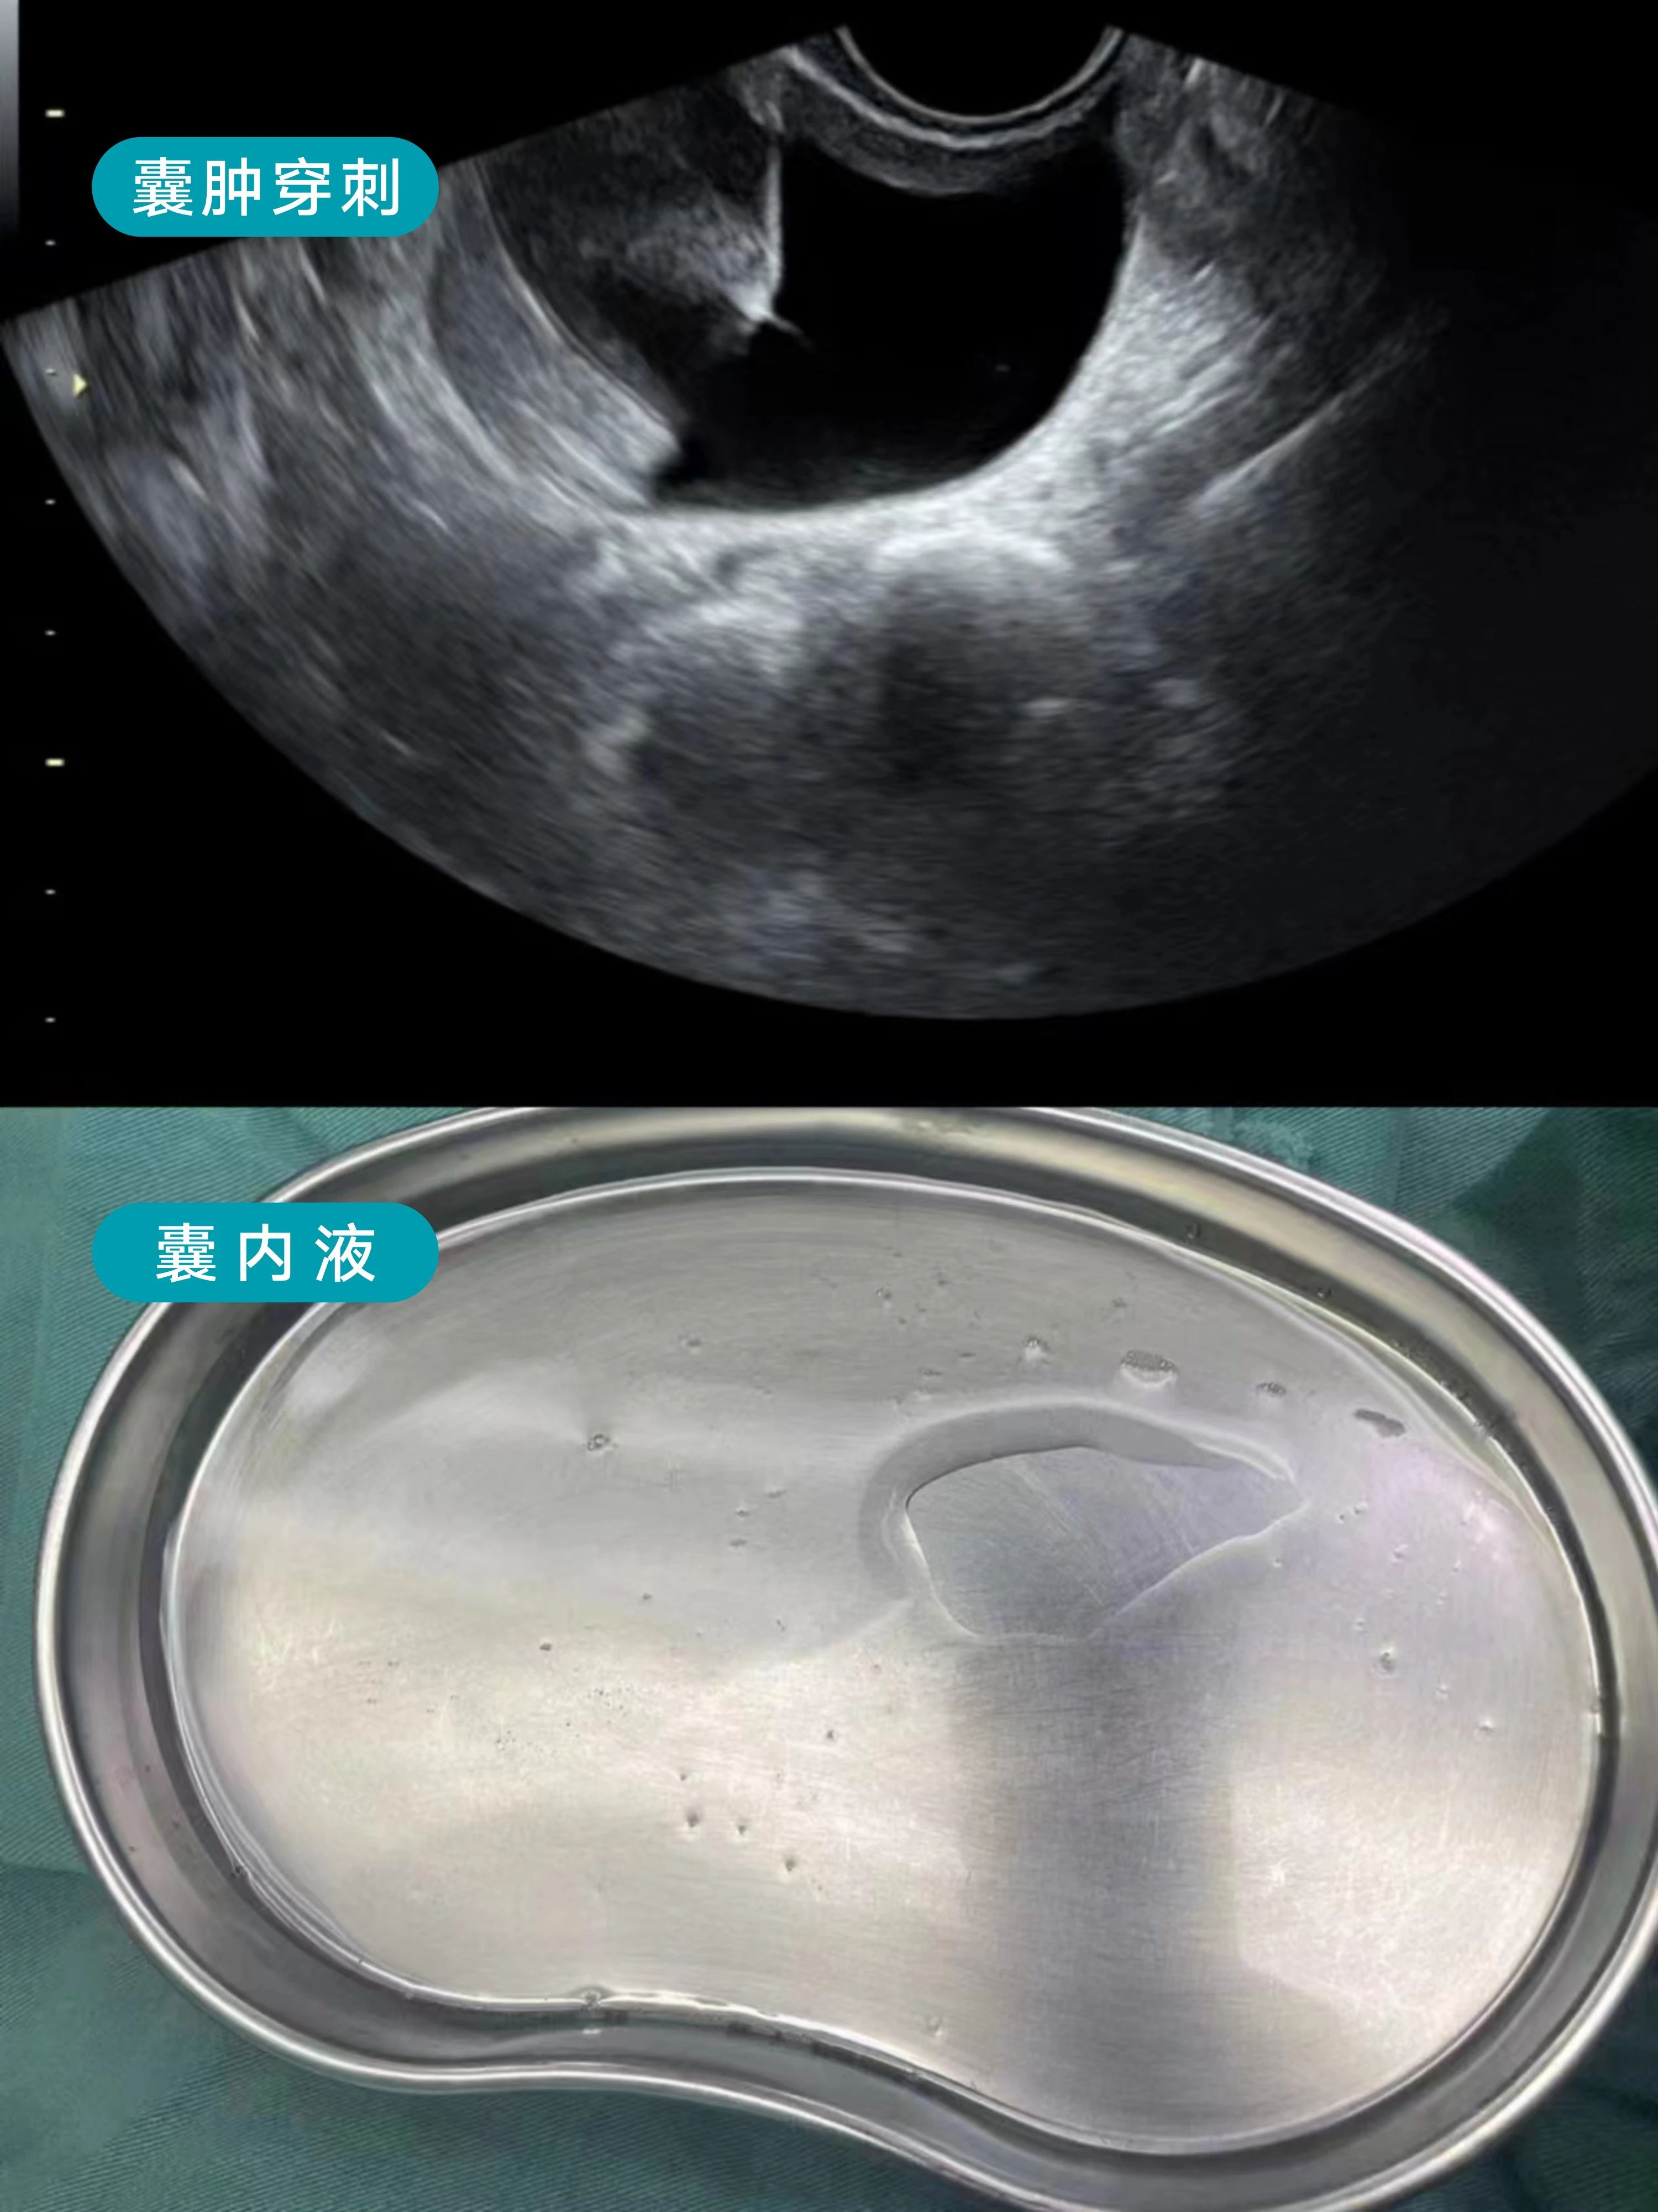

患者27岁,囊肿5cm,发现有5年了,考虑卵巢巧克力囊肿可能性大,外院给予口服地诺孕素治疗。

术前考虑巧克力样囊肿可能性大,但不排除单纯性卵巢囊肿。龚晓明教授团队给这位女士采取了日间手术,穿刺液是清亮液体,行卵巢囊肿无水酒精固化治疗,囊内液送病检查找瘤细胞。

该方法创伤小,疗效好,体表不留疤痕,及早发现及早对症治疗,深受患者好评。该患者表示,如果之前就遇到龚晓明教授团队,及早做卵巢囊肿穿刺、及时诊断疾病,就避免了长期口服地诺孕素等药物了。